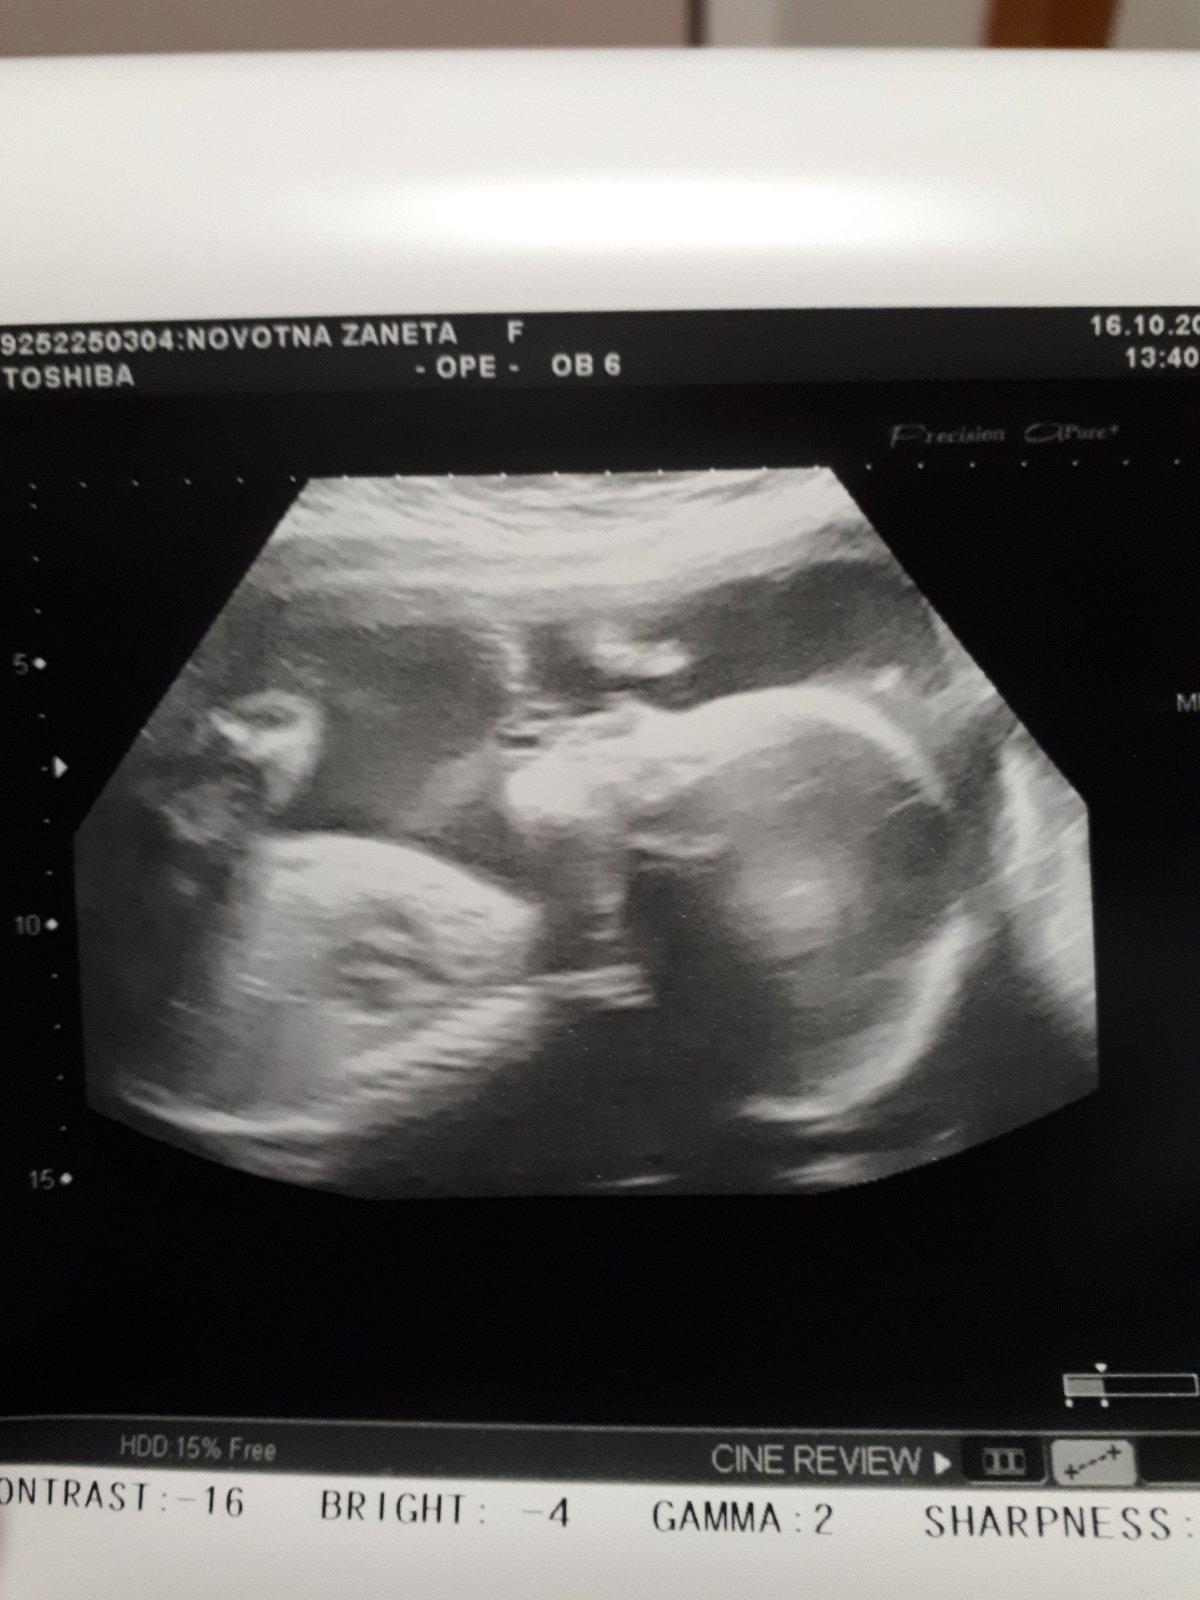

V příloze posílám malou Natálku a bříško je asi z 25tt 🙂

Jinak moc krásný bříško i foto z ultrazvuku.